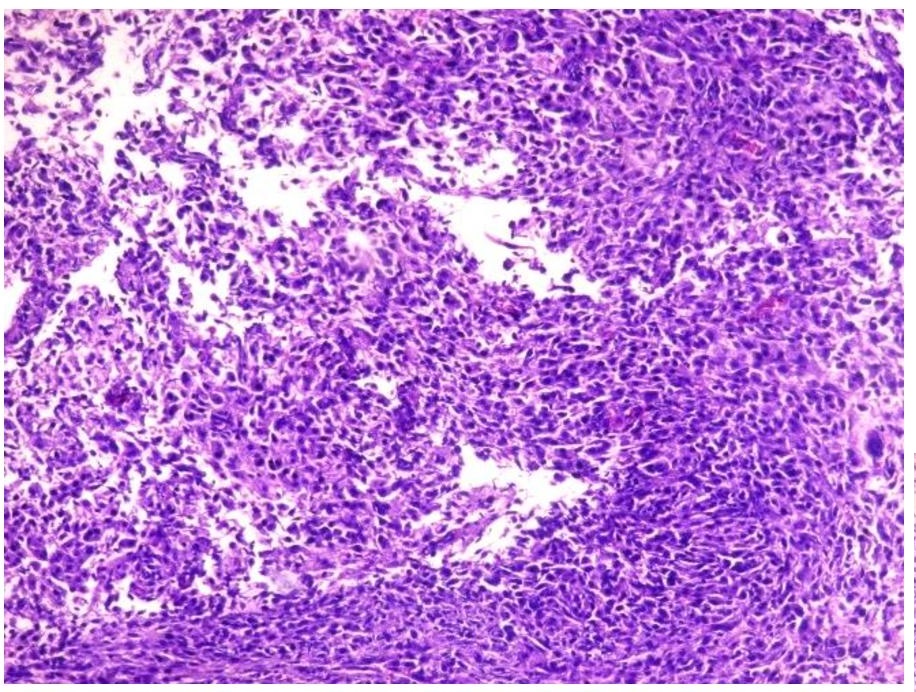

The primary mass measured 8 x 7.5 x 6 cm. The mass has cream-tan to tan, solid cut surfaces with foci of hemorrhage and necrosis. It is surrounded by a 0.2 cm-thick fibrous tissue. It is clearly-delineated from the surrounding muscle. Microscopic examination revealed the two (2) histologic components for the diagnosis of dedifferentiated chordoma. It consists of areas compatible with a conventional chordoma (Figures 1 and 2) and areas with sarcomatous differentiation (Figure 3). No transitional areas were seen between these components.

Figure 3. Dedifferentiated area with frank and pleomorphic, sarcomatous morphology (Hematoxylin and Eosin, 20x).